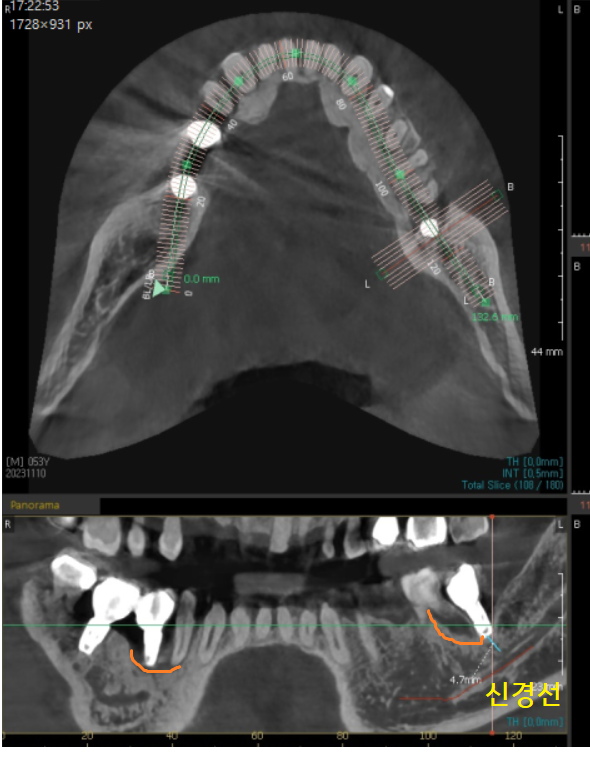

23.11.10

x-ray 상에서 잇몸 뼈가 녹은 경우에는

주변보다 까맣게 표시되는데요.

23.11.14

웅덩이가 진 것처럼 경계가 보이기도합니다.

좀더 자세한 분석을 위해 ct를 촬영

역시나 까맣게 녹은 부분이 관찰이 되죠?